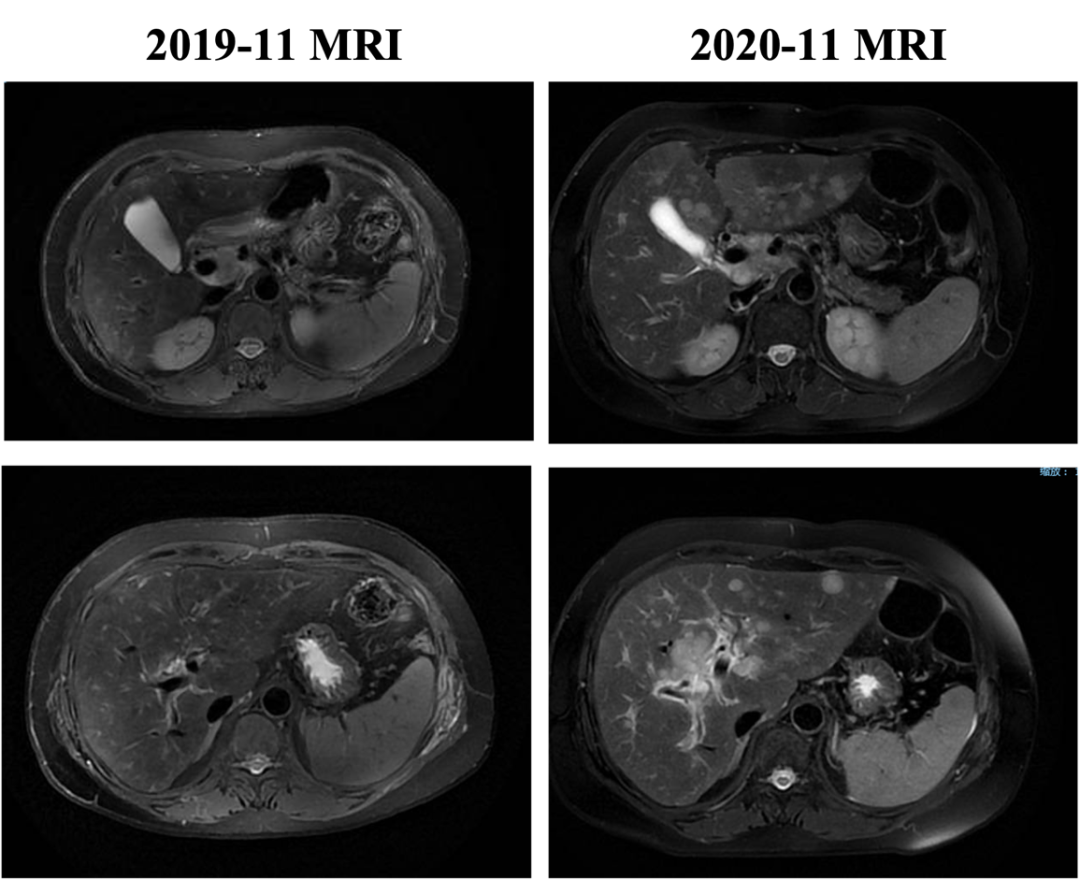

▌一线治疗:

入组MO28047临床试验(PERUSE研究),于2013-7-16开始行紫杉醇+曲妥珠单抗+帕妥珠单抗方案治疗,具体:紫杉醇175mg/m2 270mg d1;帕妥珠单抗首剂840mg,以后420mg d1;曲妥珠单抗首剂 8mg/kg 484mg,以后6mg/kg 363mg d1,Q21d。最佳疗效PR,自第10周期调整为双靶维持治疗。2015年12月(42周期时)原靶病灶维持PR,新发18mm肝转移,评效病情进展,PFS为30月。不良反应:腹泻2级,粒细胞下降2级。

图2. 一线治疗